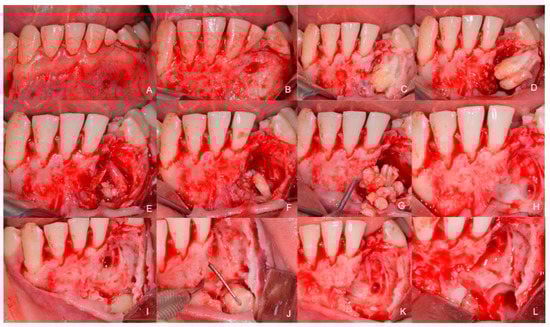

1.1. Case Number 1